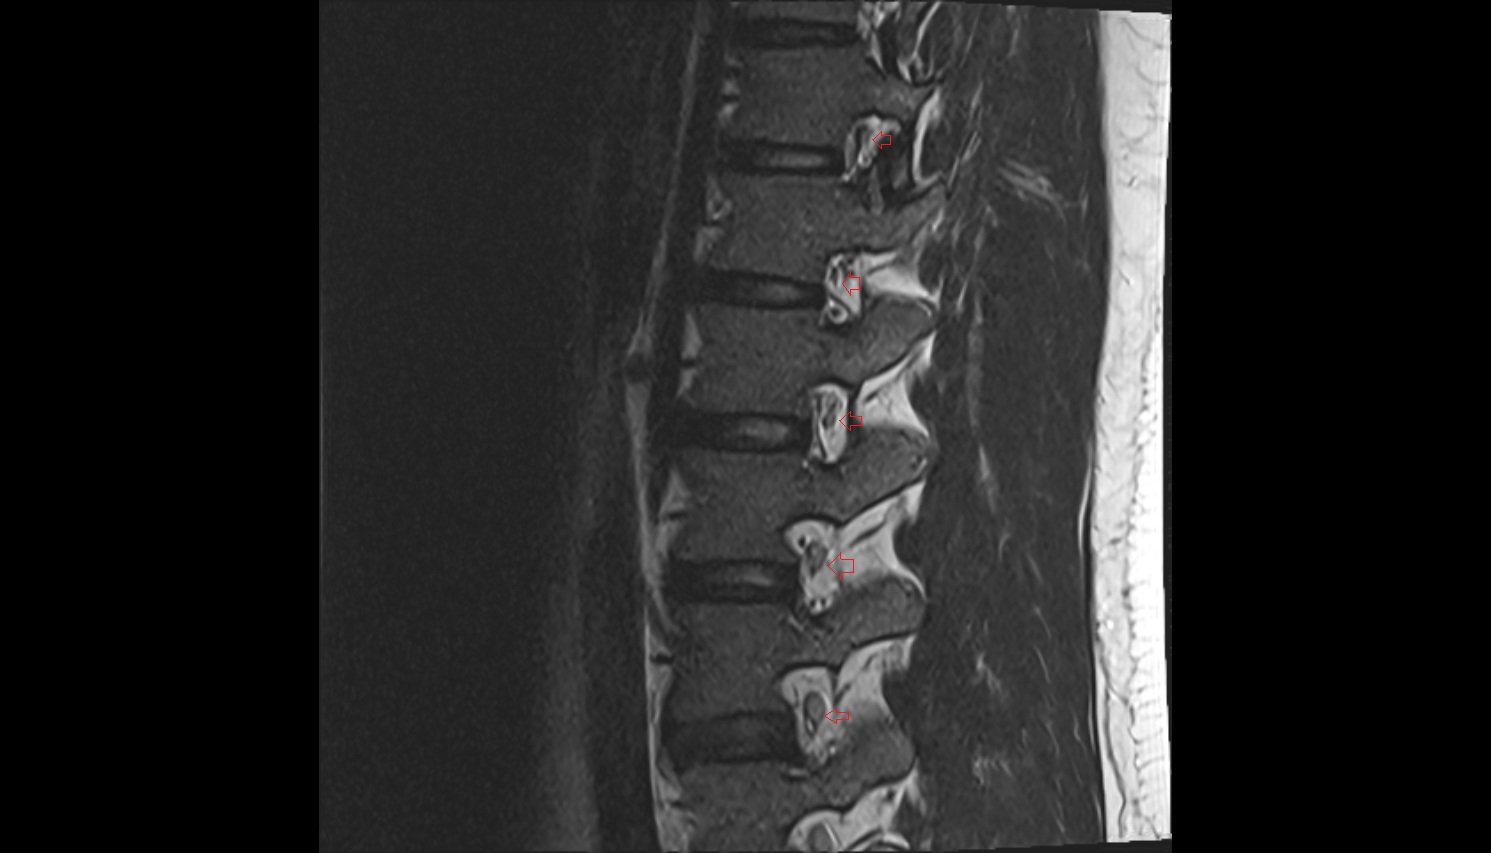

- Traversing nerve root of spinal nerve

- Exiting nerve root of spinal nerve

- Spinal dura mater

- Spinal epidural space

- Dorsal traversing nerve root

- Ventral traversing nerve root

- Dorsal exiting nerve root

- Ventral exiting nerve root

- Dorsal root ganglion of spinal nerve

- L4–L5 Intervertebral Disc

- L3–L4 Intervertebral Disc

- L2–L3 Intervertebral Disc

- L1–L2 Intervertebral Disc